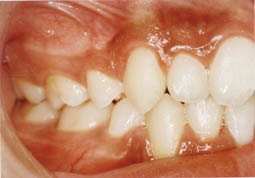

A l’examen endobuccal, il y a un encombrement dentaire avec les canines supérieures en position ectopique.

L’évaluation des arcades dentaires montre une relation de classe I molaire et canine avec un maxillaire en V, ce qui signe une mandibule verrouillée (Fig. 3-4-5).